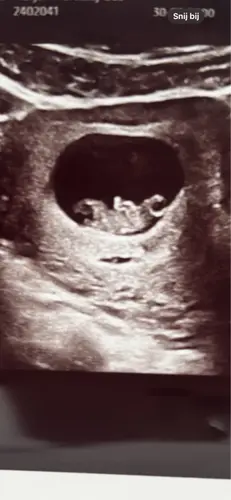

Dan doe ik ook maar mee, wat denken jullie bij die van mij. Is inwendige echo

ik denk een meisje 馃┓

Hierbij nog eentje, dit was van mn inwendige echo. Op ongeveer iets meer dan 6 weken. 馃榿

baby boy馃挋